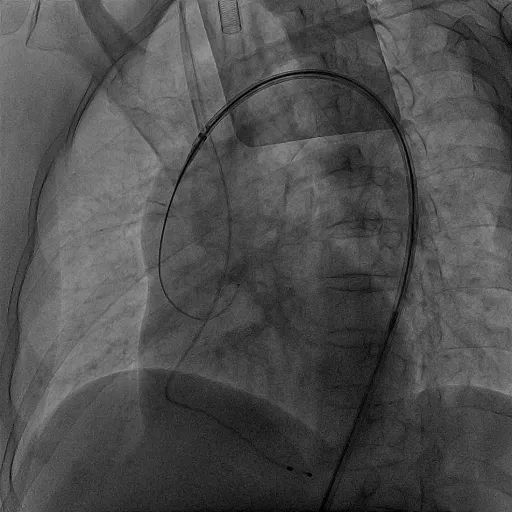

手术开始后,使用猪尾导管在无名动脉在造影辅助下选定TriGUARD3™锚定区,确认释放位置,经由左股动脉送入脑保护装置,使脑保护装置完全覆盖头臂动脉、左颈总动脉、左锁骨下动脉开口。

TriGUARD3™定位

TriGUARD3™完成释放